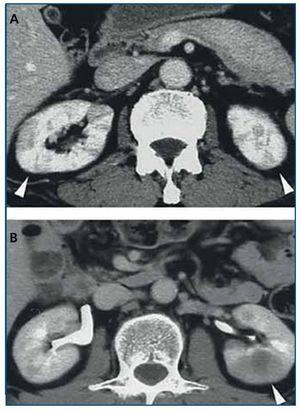

Tomografía computarizada (TC) con contraste (figura 2): las lesiones parenquimatosas son generalmente bilaterales, múltiples, y afectan de manera predominante a la corteza renal. En el 65 % se presentan como pequeños nódulos corticales periféricos redondeados, hipovasculares, de baja intensidad, invadiendo la cápsula pero sin malignidad en el examen histológico21. Otras veces se ven lesiones cuneiformes o difusas irregulares o grandes masas solitarias (pseudotumor inflamatorio)19-21 o incluso una masa quística42. La pielitis se insinúa como un engrosamiento difuso de la pared de la pelvis con una superficie lisa intraluminal21. Puede también manifestarse como una hidronefrosis22,27.

Figura 2. Tomografía computarizada con contraste. A) Múltiples lesiones cuneiformes de baja intensidad en ambas corticales renales; B) Pseudotumor inflamatorio en el riñón izquierdo. Adaptado con permiso de: Macmillan Publishers Ltd: Kidney Int19, copyright 2010.